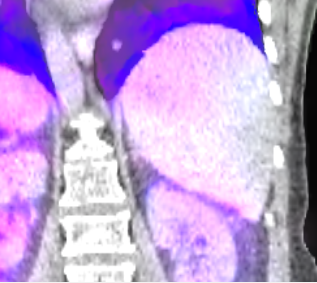

The mean DICE coefficients of the single-atlas registration of the liver and lung masks to the new static patient yield satisfying values of 0.860.12 and 0.960.09. Note the clearly different scan ranges of the data sets (Fig. 2a). The animation of the relevant structures is shown as an example in Fig. 3, using a variable real breathing signal of the target patient (Fig. 2b). In the puncture-relevant liver region, the patient’s breathing states are simulated plausibly for the 4D reference patient (Fig. 3) and, more importantly, the 3D patient (Figs. 4, 5), to which the motion model of was transferred333Demo movie, click here.

We achieve qualitatively plausible results for the liver area in this feasibility study. In the upper thorax especially at the rib cage in neighborhood to the dark lungs stronger artifacts can occur (Fig. 5c). They are due to problems in the inter-patient registration that is a necessary step for the transfer of the motion model. The non-linear deformation sometimes is prone to misaligned ribs. The same is true for the lower thorax with perforation first of the liver and then diaphragm (Fig. 4c). Further optimization have to be carried out as artifacts can appear on the high contrast lung edge (diaphragm, ribs) with a small tidal volume. For liver punctures only, the artifacts of smeared ribs are minor as can be seen in Fig. 4.